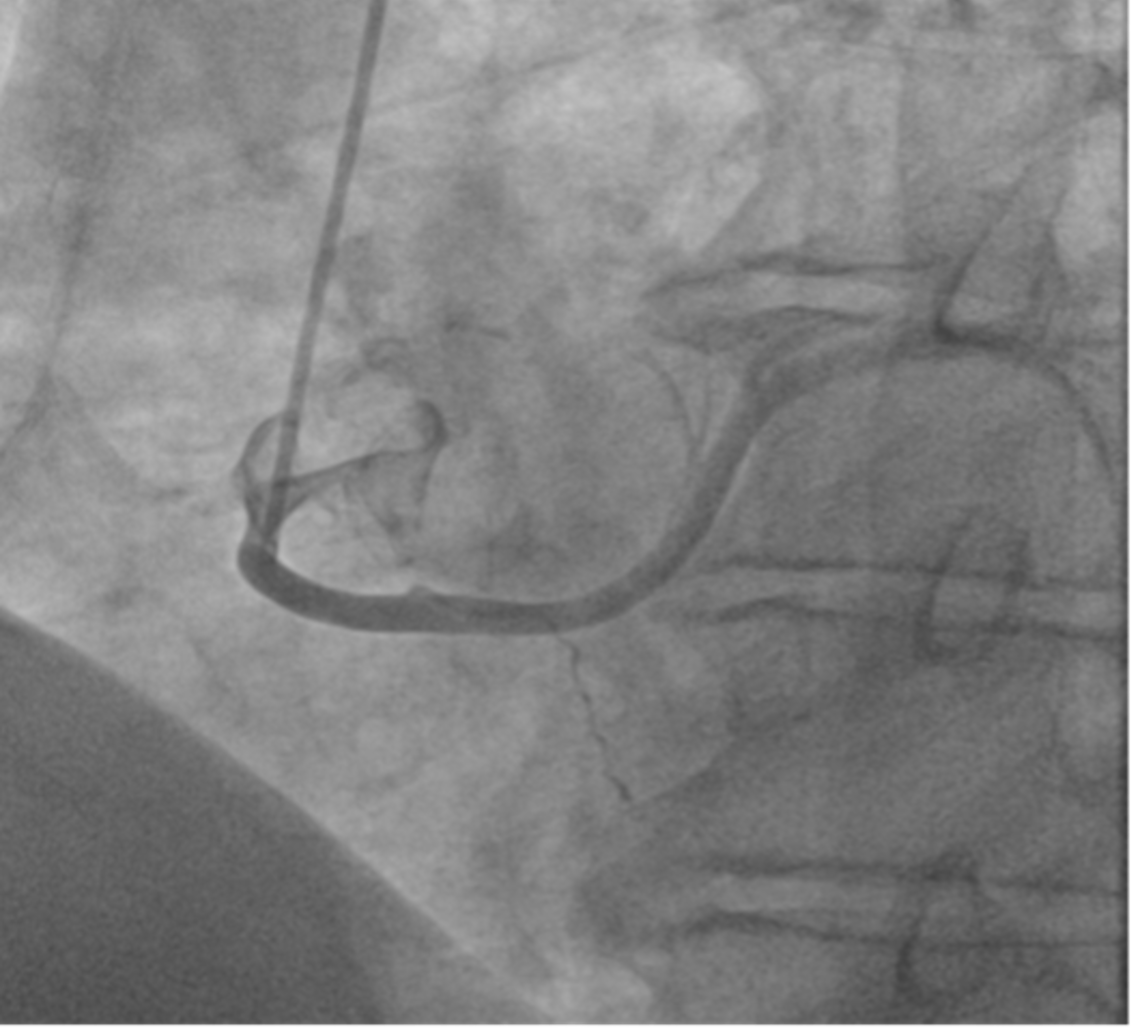

Background: Anomalous aortic origin of coronary arteries (AAOC) is a congenital condition that may affect the main three epicardial coronary vessels. The estimated prevalence of CCAs is variable, ranging from 0.21 to 5.79% based on angiography, CT, autopsy. Aim and methods: We retrospectively investigated all the angiographies and CTs performed over a 12 month-period between 2023 and 2024 at our peripheral referral center, which serves suburban areas of five cities. The aim was to assess the clinical incidence and implications of AAOC while evaluating the indications for these imaging examinations. Results: Among a total of 1100 coronary angiograms and 150 CTs, AAOC was found in 8 cases, with 4 by the former (0.37%) and 4 (2.7%) by the latter. In the cath lab, AAOC was often an incidental finding in patients with cardiovascular risk and suspected ischemic coronary artery disease. Three patients presented anomalous origin of the left circumflex artery (LCX) from the right sinus of Valsalva (Figures 1 and 2) and one patient had a left anterior descending artery (LAD) originating from the LCX. In patients diagnosed via CT, the cohort was younger, with presentations including electrocardiographic or echocardiographic abnormalities. One patient showed coronary arteries originated from the sinotubular junction (STJ). Another patient had a retroaortic LCX originating from the right sinus of Valsalva alongside an intramyocardial LAD. Two patients presented with a right coronary artery (RCA) originating from the left sinus of Valsalva (Figure 3). All patients were discharged without further interventions and were placed on routine follow-up schedules. Conclusions: AAOC remains a poorly understood condition with potential clinical implications. This small investigation provides a picture of the clinical incidence of AAOC in our geographical area, aiming at increasing the awareness of the disease in daily clinical practice. Improved stratification of patients with AAOC is essential to optimize management and may be provided by larger outcome trials.